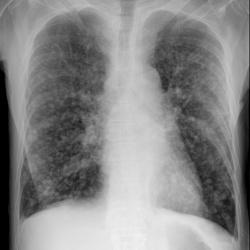

Пациент 63 года. Жалобы на слабость, кашель с мокротой.